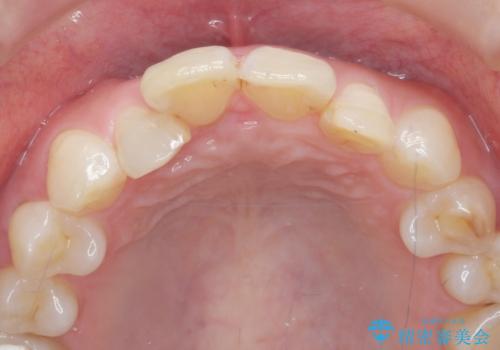

インビザラインで行う前歯のみの部分矯正

- 長年気になっていた前歯の歯並びを改善したいと、矯正治療を希望され思い切って来院されました。

費用と期間を相談し、「気になっているのは前歯だけ。」とのことでしたので前歯のがたつきのみをインビザラインで改善する矯正治療の計画を立てます。

しっかりとマウスピースの装用時間を守っていただき、非常にスムーズに治療を終了することができました。